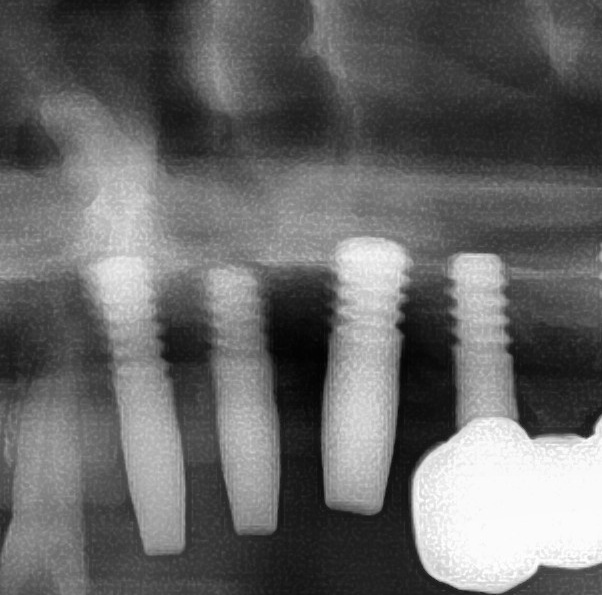

開けた穴に、専用道具を使ってネジを締めるように長さ2センチ程のインプラントを骨に埋め込んでいきます。

続けて他の歯も同じように植立していきます。

インプラントオペでは、複数本を植立する場合でも、当時進行はせず、1本ずつ同じ工程を繰り返して植立します。

しっかりとインプラント埋め込まれた後は、動揺がないか、噛んだ時に当たらないかなどを確認して、最後にパノラマ写真を撮影して今回のオペは終了となりました。